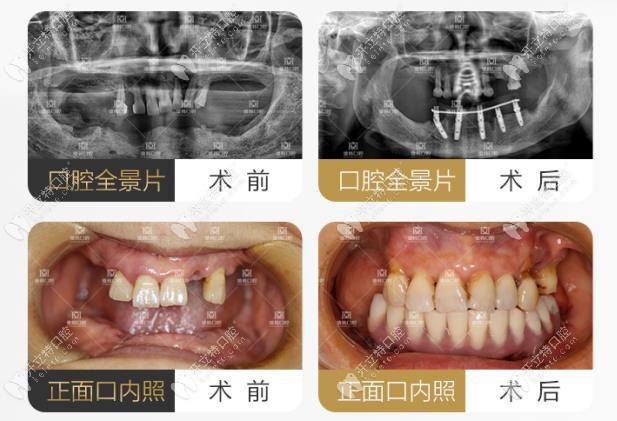

上下頜牙齒松動,采用all-on-4做全口即刻負重案例

案例主角是一位78歲的高齡患者,因為全口上下頜牙齒全部松動,由于常年佩戴假牙,導致牙槽骨也出現(xiàn)了重度萎縮,咀嚼功能受限,特到院內(nèi)檢查。

羅薩蒂提出方案為:上下頜松動的牙齒及殘根全部拔除,采用all-on-4進行全口即刻負重技術進行當天佩戴牙冠。

羅薩蒂做all-on-4案例圖

手術當天,羅薩蒂先將殘根拔除,然后根據(jù)顧客牙槽骨條件,植入植體,當天下午就佩戴上牙冠,完成修復。